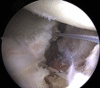

Arthroscopic Bone Block Cerclage Technique Using a Tricortical Scapular Spine Autograft for Glenoid Reconstruction in Patients With Anterior Shoulder Instability

In the treatment of anterior shoulder instability with glenoid bone loss, free bone graft transfers have proven to be a viable anatomic alternative to the commonly performed, nonanatomic Latarjet procedure. Implant-free fixation of the free bone grafts, in particular, has rendered excellent short- and long-term results. However, a drawback remains the source of the graft. We describe an arthroscopic bone block cerclage technique using a tricortical scapular spine autograft, which provides an anatomic arthroscopic glenoid reconstruction with the combined benefit of sparing the subscapularis, metal-free fixation, and intraregional donor site for autograft harvesting.